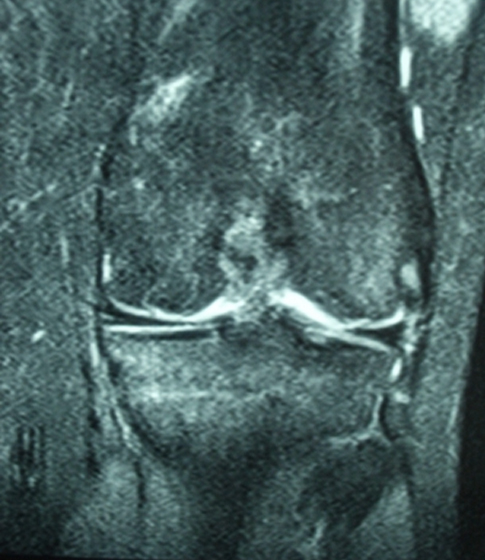

Hastanın ameliyattan sonraki birinci yıl MR tetkiklerinde ayrışmanın tamamen iyileştiği gözlendi.

Şikayetler sona ermişti ve hasta tekrar basketbol oynayabiliyordu.